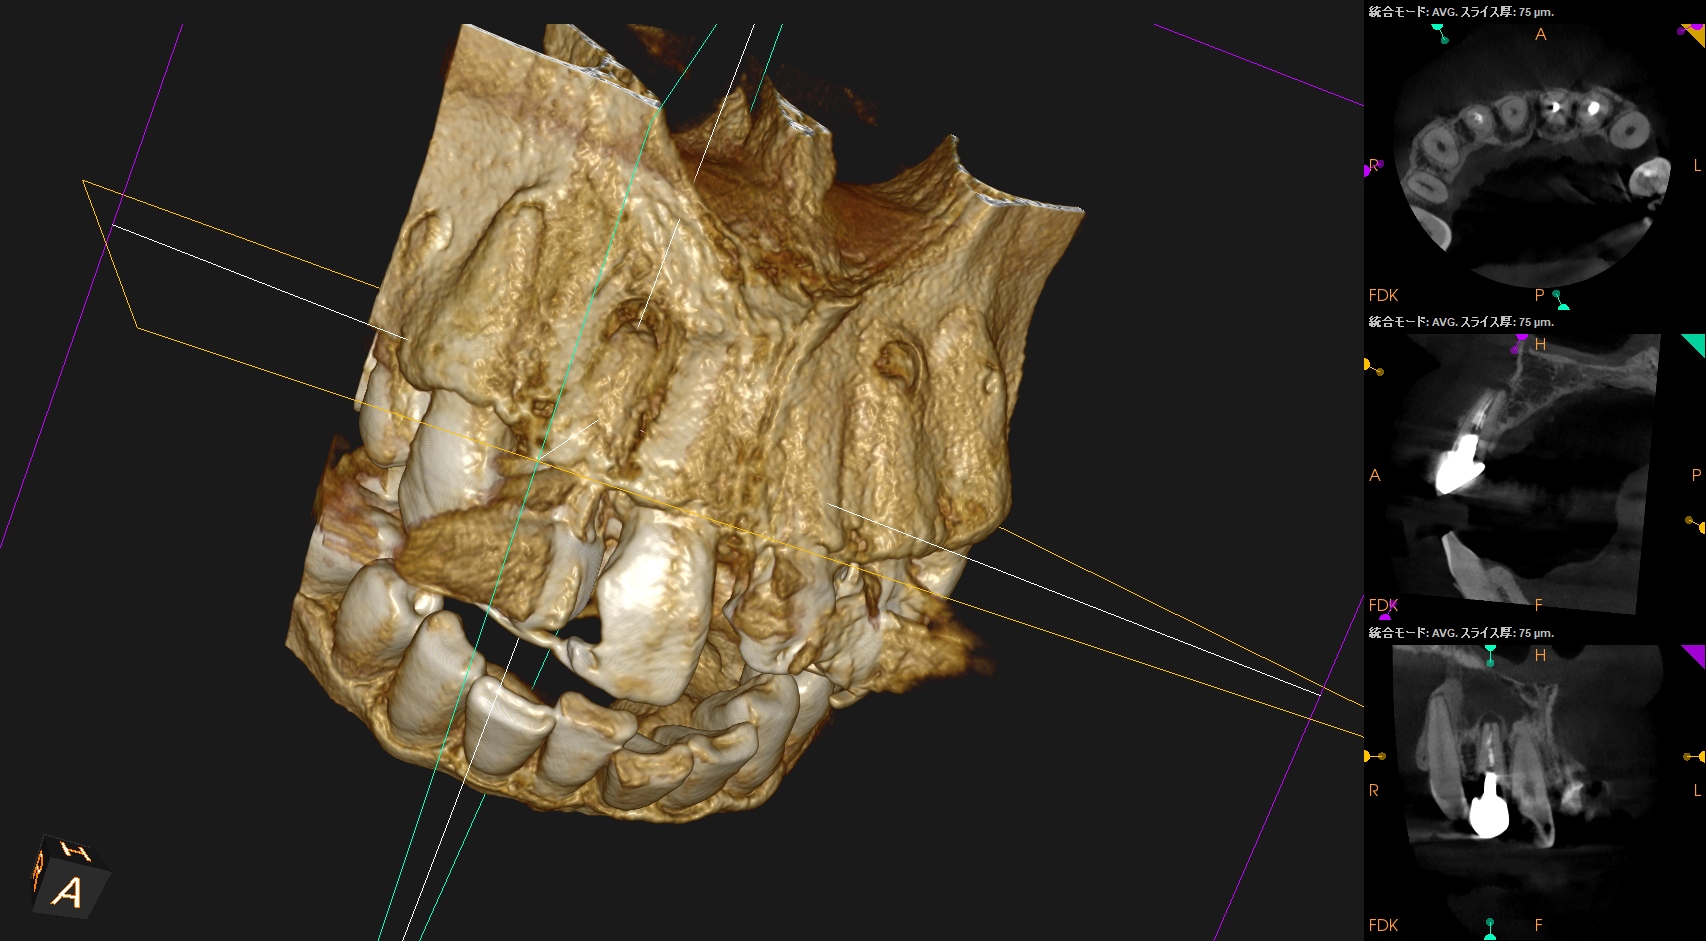

そこで、CBCTも撮影した。

#7

#10

これでも判然としかねる。

そこで、

CareStream(日本ではヨシダ社)のCBCTなら以下のようにMPR(Multi-Planar Reconstruction)画面を作成することができる。

それを過去のそれと比較してみた。

↓

このMPR画像からこの患者さんは#7,10ともに外科治療など要らないということがわかるだろう。

無論、検査の結果からそれは必要はないと言えるが、

客観的に不要であるということを患者さんに伝えるにもこの画像機能(MPR画像)は非常に有効である。

ということで今日は、このMPR画像機能について論じてみた。